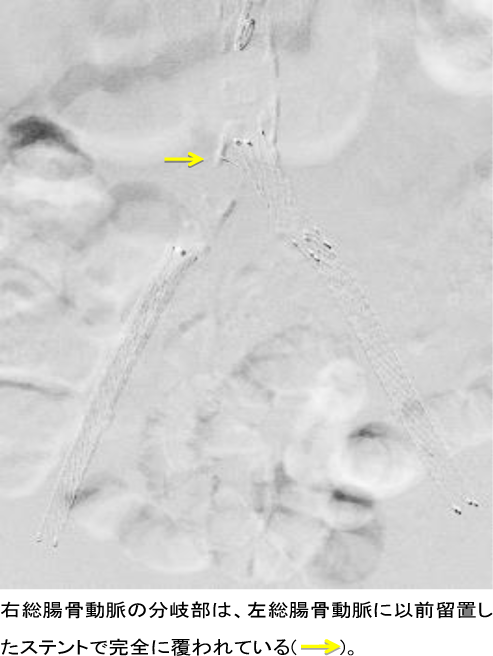

症例は75歳男性。高血圧で近医定期外来通院中、両下肢間欠性跛行を認めたため当科紹介受診。下肢ABIは左0.62、右0.73と低下。下肢動脈造影CTおよび下肢動脈血管造影検査で、両側腸骨動脈狭窄および左浅大腿動脈狭窄の所見を認め、閉塞性動脈硬化症と診断。手術適応あり両側腸骨動脈病変に対して血管内治療を施行した後、今回左下肢(浅大腿動脈)に対して血管内治療を施行した。より低侵襲で行うため、左足先(足背動脈)よりカテーテルを挿入し治療した。